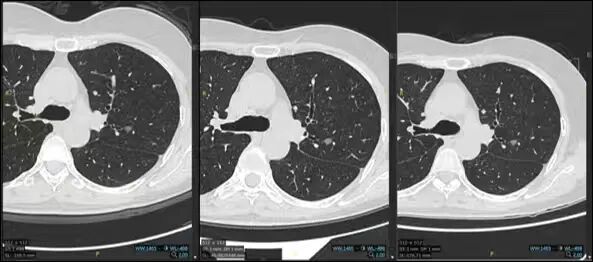

(1)吸收消散——来去匆匆的客人

许多结节本质是炎症或感染,在人体免疫系统及外用抗炎药物的作用下,它们会逐渐缩小,甚至完全消失。这类结节通常边缘模糊,随访复查时可能会给我们带来惊喜。

(2)稳定不变——和平共处的邻居

部分结节属于陈旧性病灶、良性肉芽肿或良性肿瘤,它们在长时间内大小和形态都保持稳定,没有明显变化。

(3)增长/进展——扩张地盘的对手

也有部分结节随着时间的延长,出现直径持续增大、内部实性成分增加或是边缘出现分叶、毛刺等恶性特征,这提示其具有活动性,恶性风险升高。